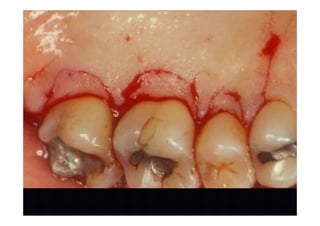

Surgery

Removing granulation tissue and

osteoplasty

3 months control

7 months control